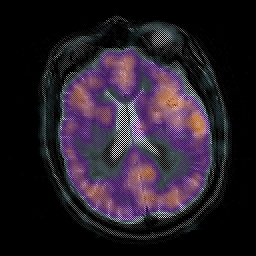

Subacute Stroke, overlay -- Slice #15

[Home][Help][Clinical] Slice 15